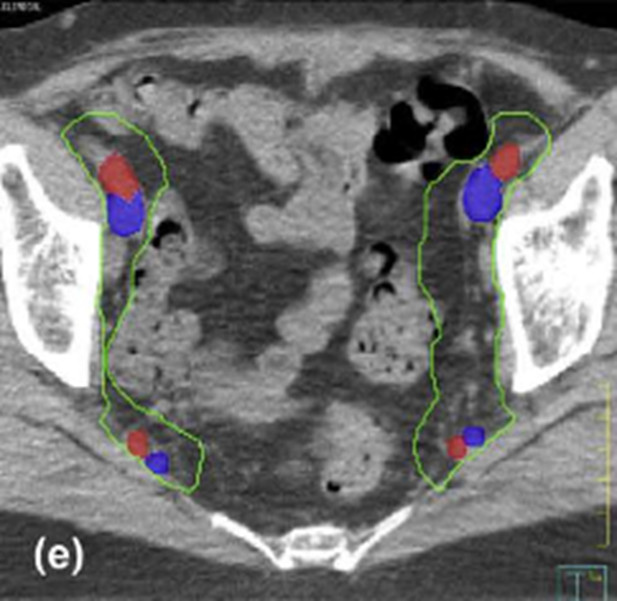

Na poniższym skanie TK strzałką oznaczono węzły chłonne: